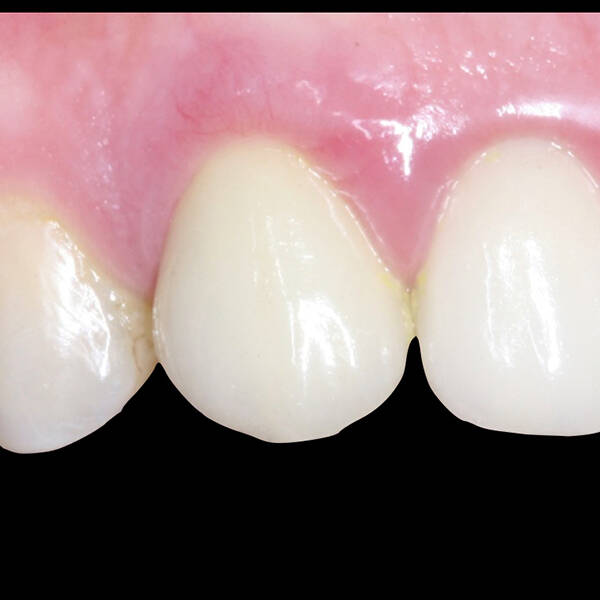

- Conforto e Estética: A prótese provisória é funcional e visualmente semelhante aos dentes naturais.

- Preservação óssea: A técnica estimula o osso, prevenindo sua reabsorção, comum em casos de perda dentária.